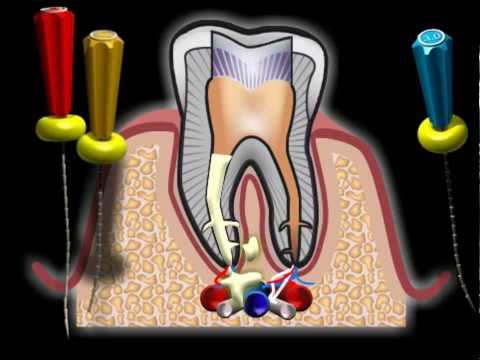

Стоматолог может использовать специальные инструменты и техники для удаления материала, такие как ультразвуковые аппараты или микроскопы.

Временные пломбировочные материалы - Temporary filling materials - Материаловедение